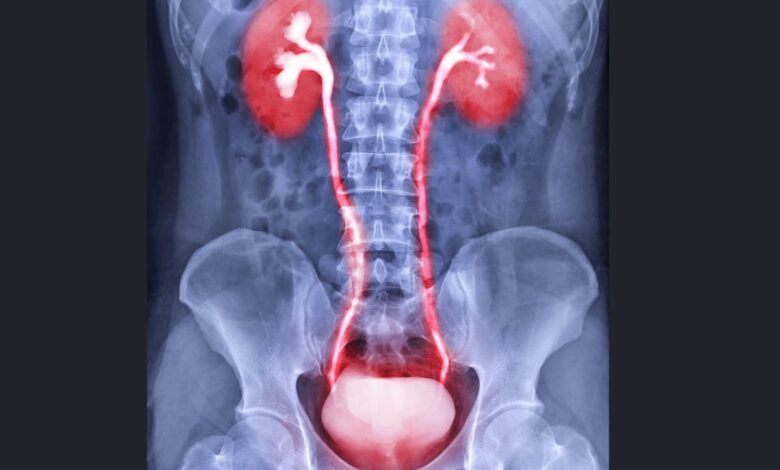

O que é a Infecção Urinária?

A infecção urinária é uma infecção bacteriana que pode ocorrer em diferentes partes do sistema urinário:

- Uretrite – Infecção na uretra

- Cistite – Infecção na bexiga (a mais comum)

- Pielonefrite – Infecção nos rins (mais grave)

- Prostatite – Infecção na próstata (mais comum em homens)

- Orquite – Infecção nos testículos

- Epididimite – Infecção no epidídimo

A maior parte das infecções é causada pela bactéria Escherichia coli, que vive naturalmente no intestino, mas pode migrar para a uretra e bexiga.